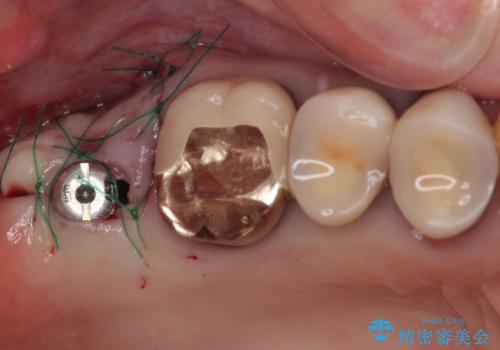

抜歯後2ヶ月でのインプラント埋入を行いましたが、骨の再生は不十分でした。

骨量は不十分でしたが、デンサーバーを用いることで無事に埋入することができ、その後は速やかに補綴治療を行うことができました。